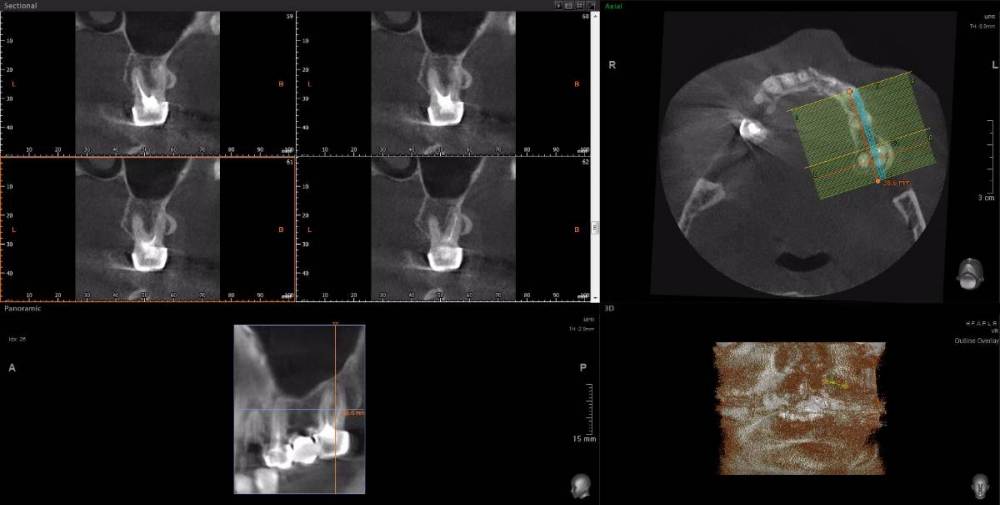

Dude Опубликовано 1 апреля, 2021 Поделиться Опубликовано 1 апреля, 2021 По плану в 1 этапе, кроме остального: лечение каналов и укрепление их стекловолоконными штифтами: 16, 25, 27, 44, 47; имплантация 14, 15, 17, 12, 11, 21, 22, 24, 26, 36, 37, 46, 45. Во 2 этапе (через 5-6 месяцев) установка коронок. Лечение в другой стране. Чтобы сократить длительность первого этапа, предложили лечение зубов сделать на 2 этапе. Очень засомневался, можно делать имплантацию с невылеченными зубами? Ссылка на комментарий

Dude Опубликовано 1 апреля, 2021 Автор Поделиться Опубликовано 1 апреля, 2021 https://disk.yandex.ru/d/6d0pmZ1zArn1Og Так? Ссылка на комментарий